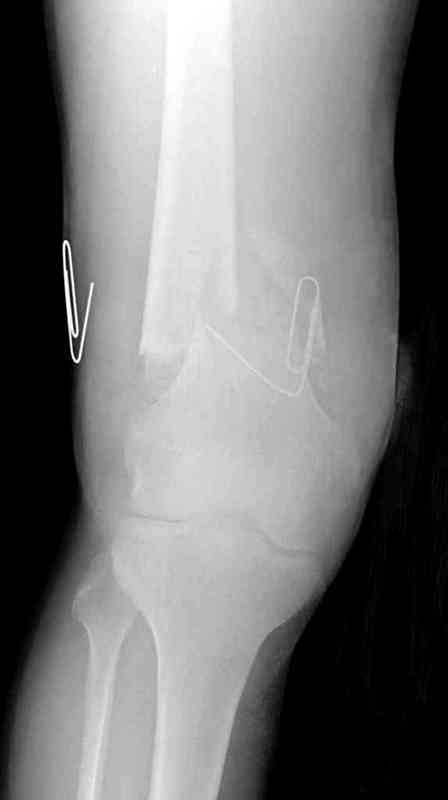

> мероприятия по сближению краев раны резиновой стяжкой.

Не могли бы Вы рассказать о технике наложения и методике использования "резиновой стяжки"? У нас сохранилось несколько коробок "сосудистых" резиновых полосок (гуманитарная помощь). Мы используем их как "держалки" для сосудов и нервов (фото в прищепке). Вы продемонстрировали иное применение. Или это другие "стяжки"?

Нет, те же сосудистые держалки, их можно применить для сближения краев ран, только надо иметь stapler для ушивания. Резина прикрепляется с помощью скоб по краям раны (как на рисунке) и затягивается. Сверху вакуум VAC, через пару дней почти приближенные края

закрывается без натяжения.